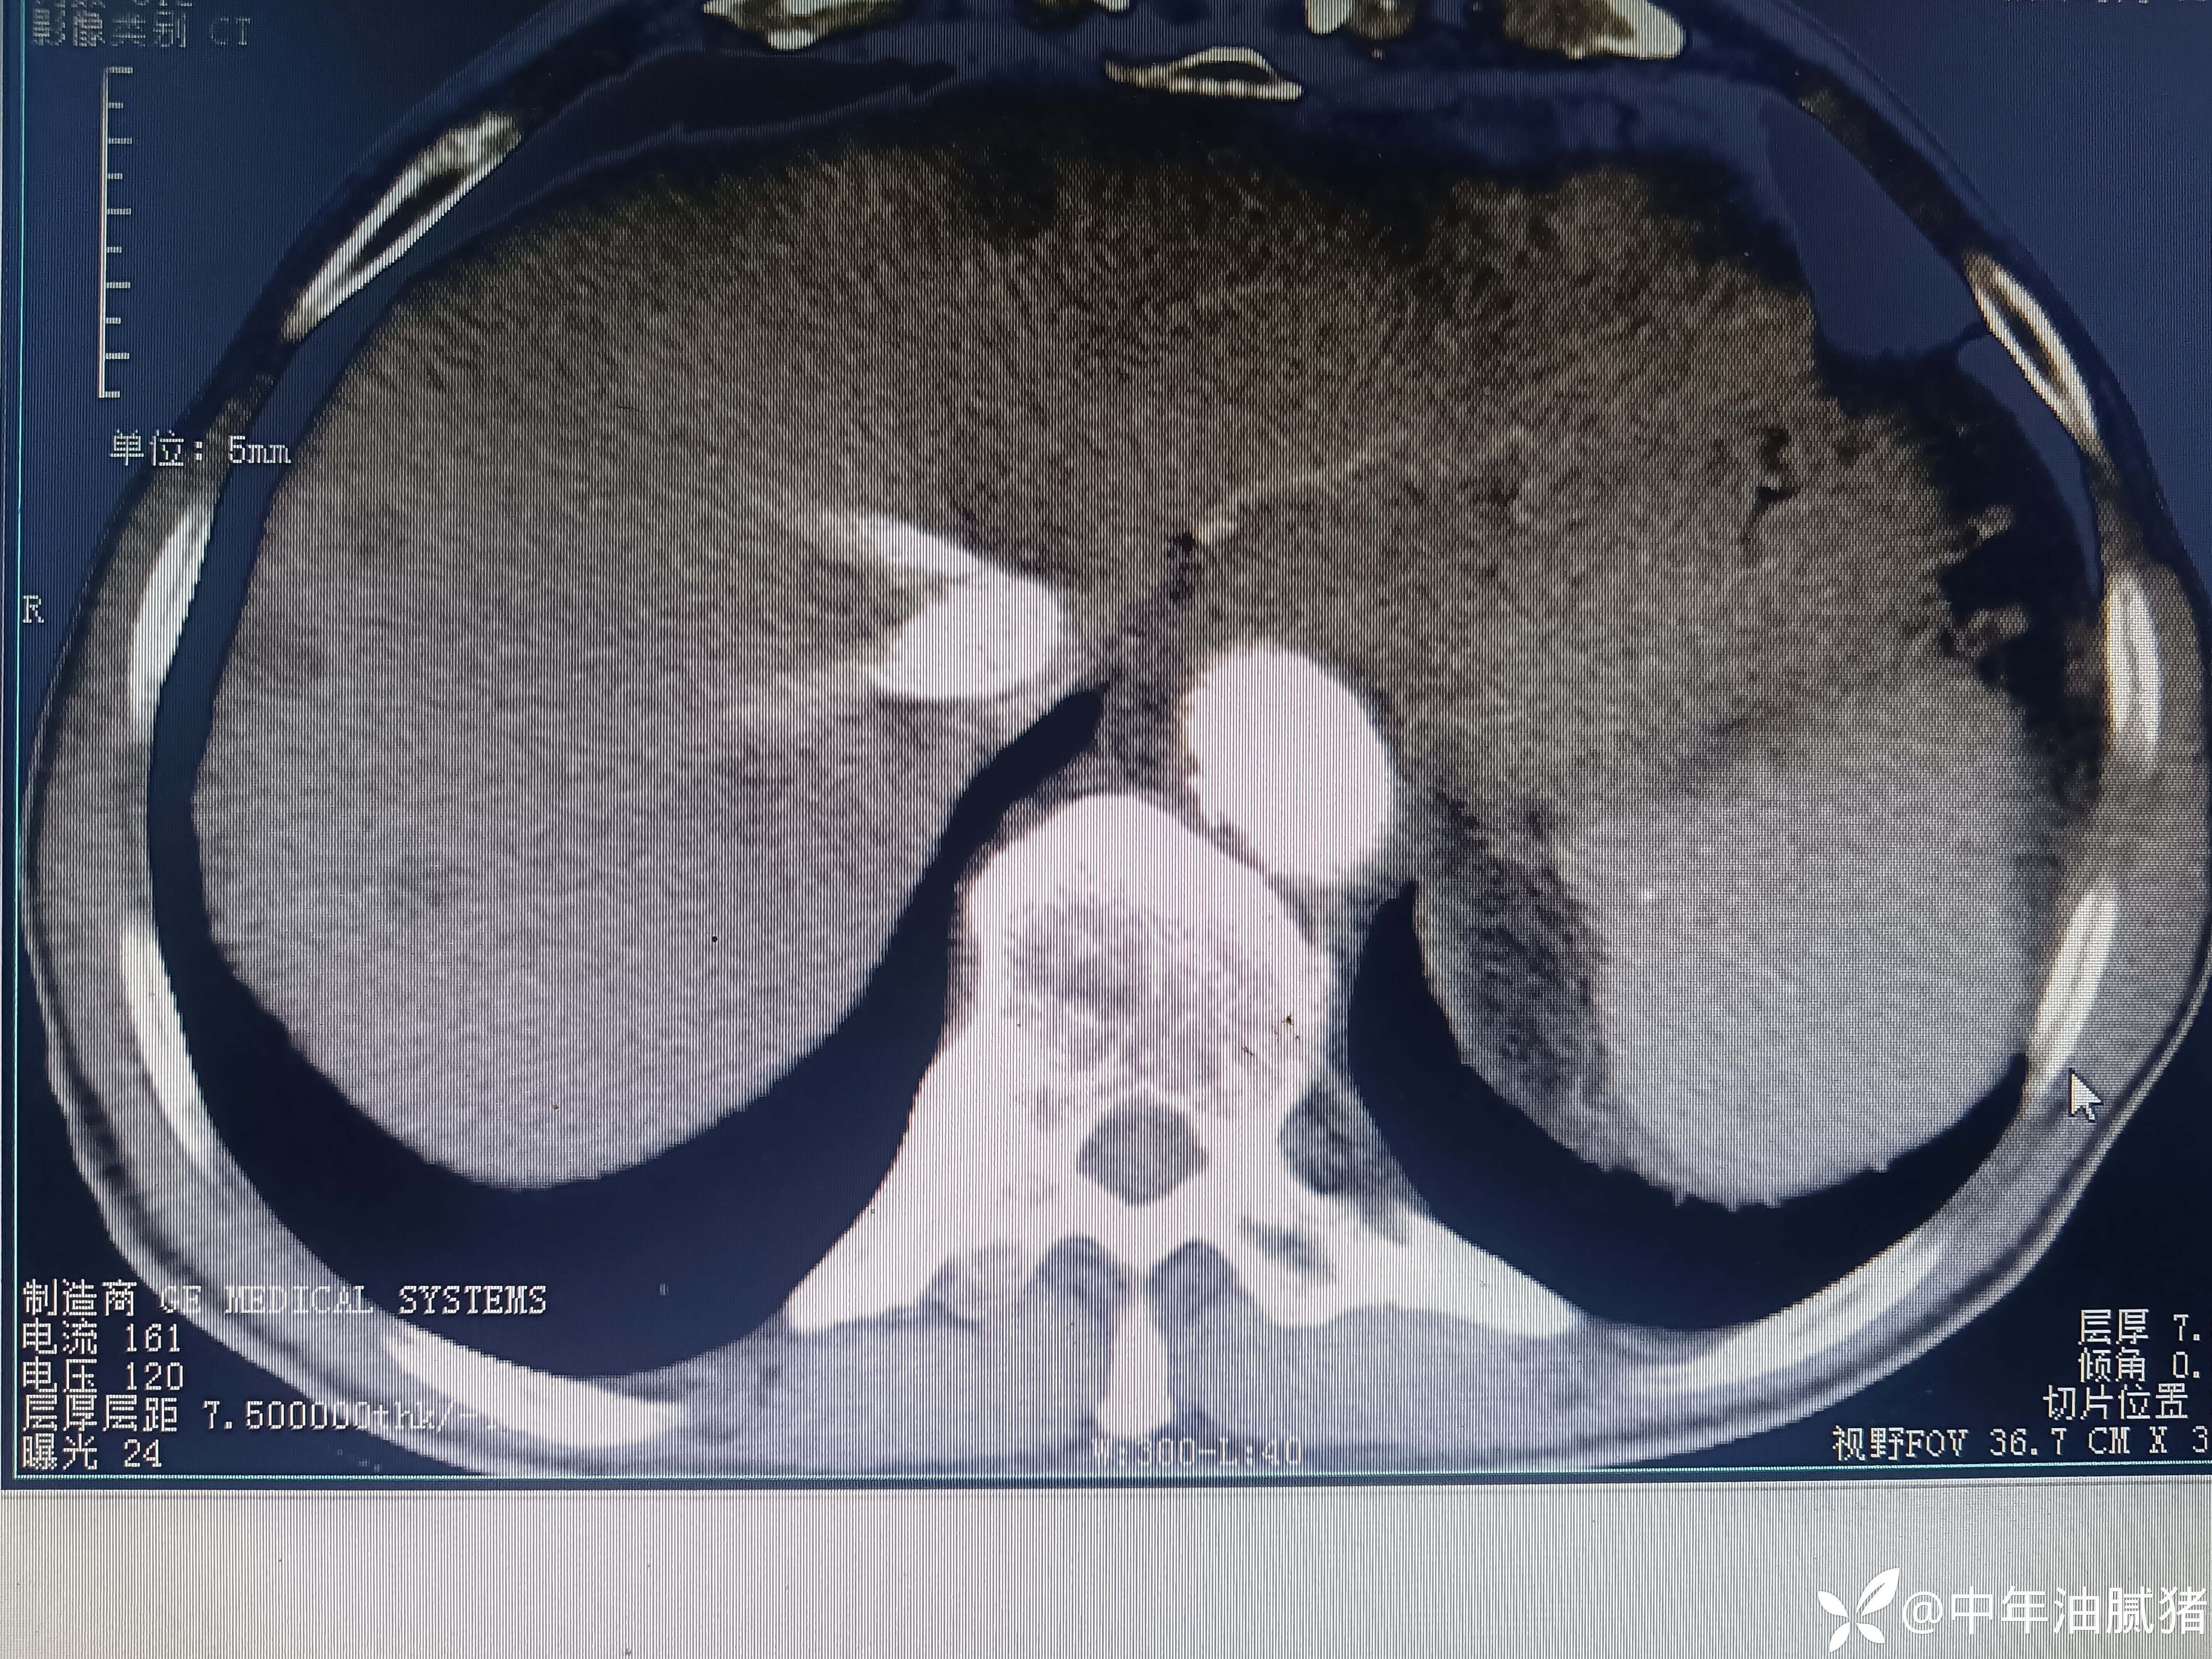

肺ct看到肝内病灶,行增强检查

男,72岁,感胸痛7天,不剧,咳嗽时略明显,有吸烟,行肺ct报告如下

建议增强ct.报告如下

考虑肝囊肿?让他走?

看后,我隐隐约约觉的不是肝囊肿那么简单?元芳,你怎么看?狄阁老,我也是这么认为!摇人,掏起手机:喂,w主任,请帮我看看这个ct。5分钟后报告修改如下